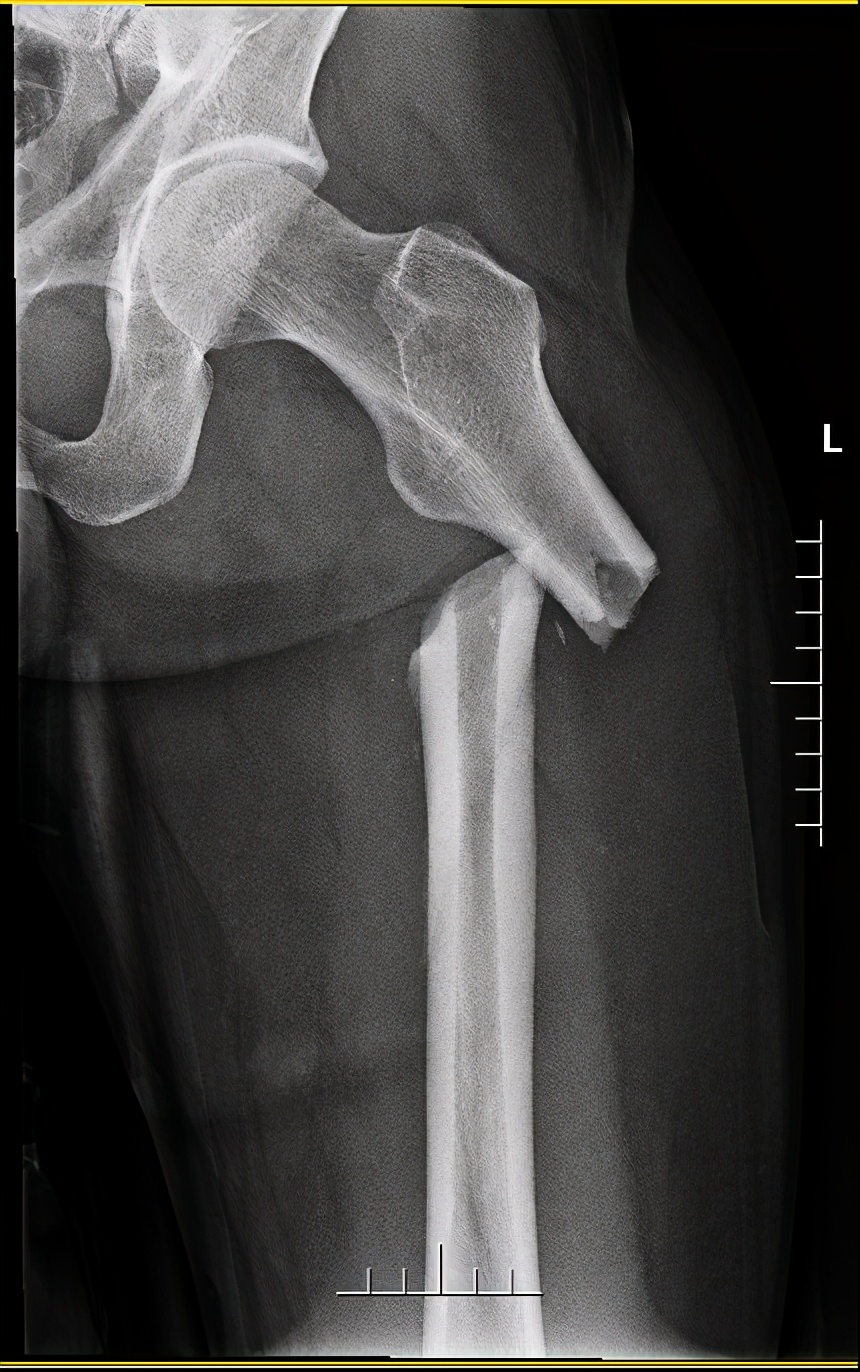

创伤小组立即全面检查病人情况并作出针对性的检查,初步诊断患者左侧开放性粉碎性胫腓骨骨折伴有左胫前动脉损伤及局部肌腱断裂,同时有左股骨干粉碎性骨折和肺挫伤。多处骨折出血量大,血管损伤又导致左足供血不足,若得不到及时的救治,患者随时面临着截肢甚至死亡的威胁。

结合患者的病情及患者的心理状态,潘刚明主任、董君博副主任医师、鲜安福护士长一方面多次组织团队成员,遵照微创手术技术理念(MIPPO)、损伤控制外科(DCS)理念及快速康复(ERAS)理念,制定个性化的手术、护理方案,并反复耐心地向患者说明病情及良好预期、做好心理疏导使患者配合治疗。在多科室配合及医患协作下,左股骨粉碎性骨折的微创闭合复位内固定手术及左胫腓骨粉碎性骨折微创经皮复位内固定术顺利完成。